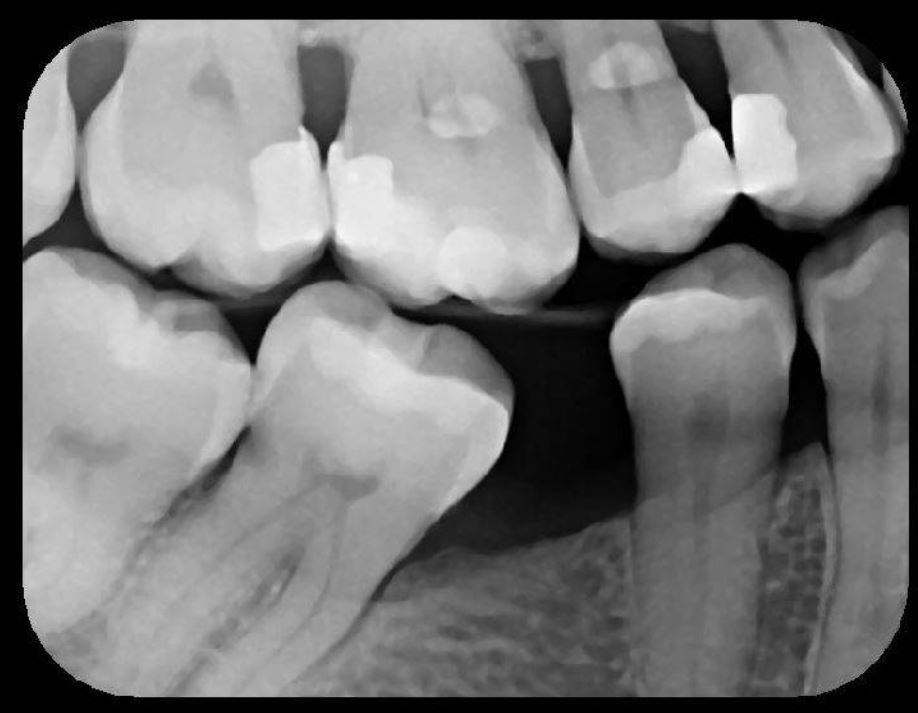

X-Ray 2: How many caries are present?

(Required)

X-Ray 2: How many PAP's are present?